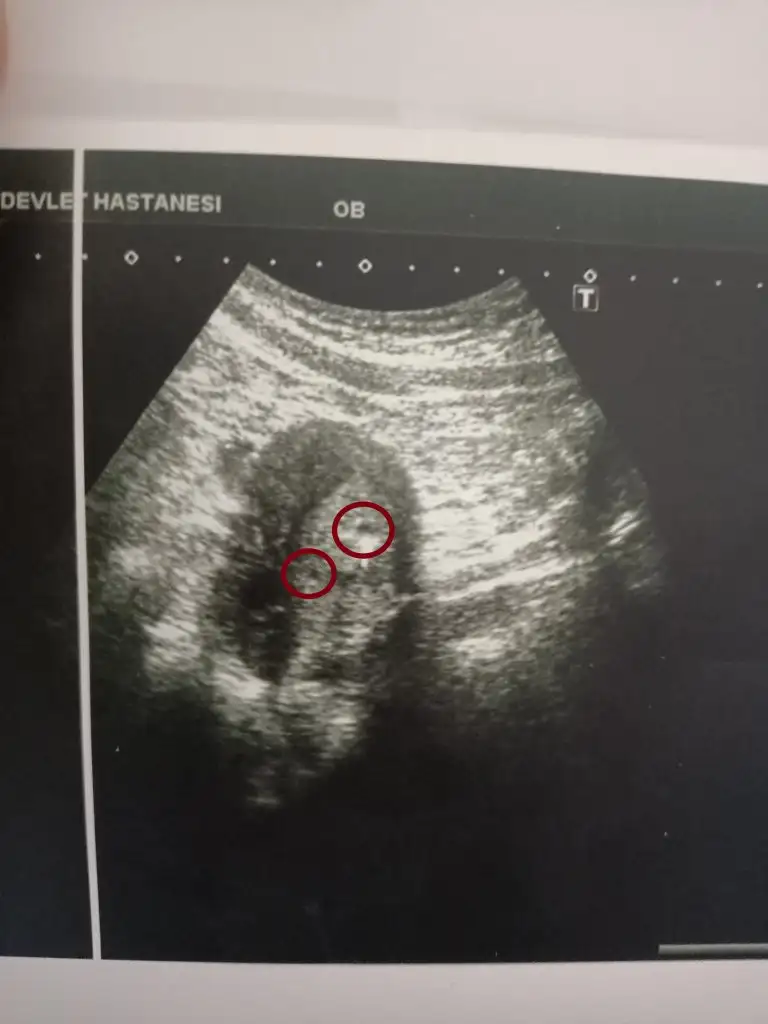

Kızlar dün doktora gittim 4+5 teyim daha çok erken ama doktor ufacık bı kese görüyorum dedi. Üstte işaretledigimden bahsetti kese bu dedi. Kan sonuçlarımda biraz yüksek. Sizce peki doktor üstte işaretledigim noktaya kese dediğine göre alta benim işaretledigim noktada keseye benzemiyor mu sizcede??? Siz ne düşünüyorsunuz üstteki işaretli alan kese peki alttaki işaretledigim kısımda da ikinci bir kese olabilir mi?? Sizce ikiz olabilir mi?